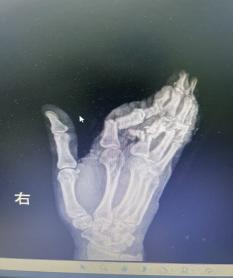

荊楚網(wǎng)(湖北日報網(wǎng))訊(通訊員 嚴玉嬌 戰(zhàn)慧瑩)2026年3月1日16時09分,一陣急促的鳴笛聲在街道上響起,一輛轎車跨越1個多小時的路程從云夢縣城飛馳而來,緊急停靠在湖北航天醫(yī)院急診科門前。車上,34歲的余女士(化名)面色蒼白,她的右手被厚厚的紗布包裹,殷紅的血跡已滲透多層敷料——她的右手食指、中指、無名指三指完全離斷,小拇指嚴重損傷,無力地垂在一旁。

1小時前,余女士還在工作,一個不留神,粉碎機擠壓到了她的手,右手瞬間卷入機器。劇烈的疼痛襲來,當(dāng)她抽出手時,眼前的一幕讓她幾乎暈厥——食指、中指、無名指已完全離斷,只有少許皮膚還連著,小拇指也血肉模糊。

抵達醫(yī)院時,航醫(yī)骨外科值班醫(yī)生已接到通知,在急診待命。接到余女士的那一刻,值班醫(yī)生迅速上前為她查看傷情“您別擔(dān)心,一切有我們”,經(jīng)快速檢查,診斷明確:余女士的右手多指完全離斷傷。這是一類極為嚴重的手部創(chuàng)傷,斷指再植手術(shù)的黃金時間僅有6-8小時,一旦治療時間稍有延誤,難以保證手指存活。

手術(shù)的難度超乎想象:

血管細如發(fā)絲:手指的動靜脈直徑僅0.3-0.8毫米,醫(yī)生需要在顯微鏡下用比頭發(fā)絲還細的縫線進行吻合;

多指同時再植:余女士食指、中指、無名指三指離斷,需同時重建血運,給手術(shù)醫(yī)師的精力和體力帶來極大考驗;

小拇指皮瓣修復(fù):小拇指軟組織缺損嚴重,醫(yī)生將精心設(shè)計皮瓣覆蓋創(chuàng)面,避免術(shù)后壞死;

骨折內(nèi)固定+肌腱神經(jīng)修復(fù):不僅要讓手指“活”,更要讓手指“能用”。